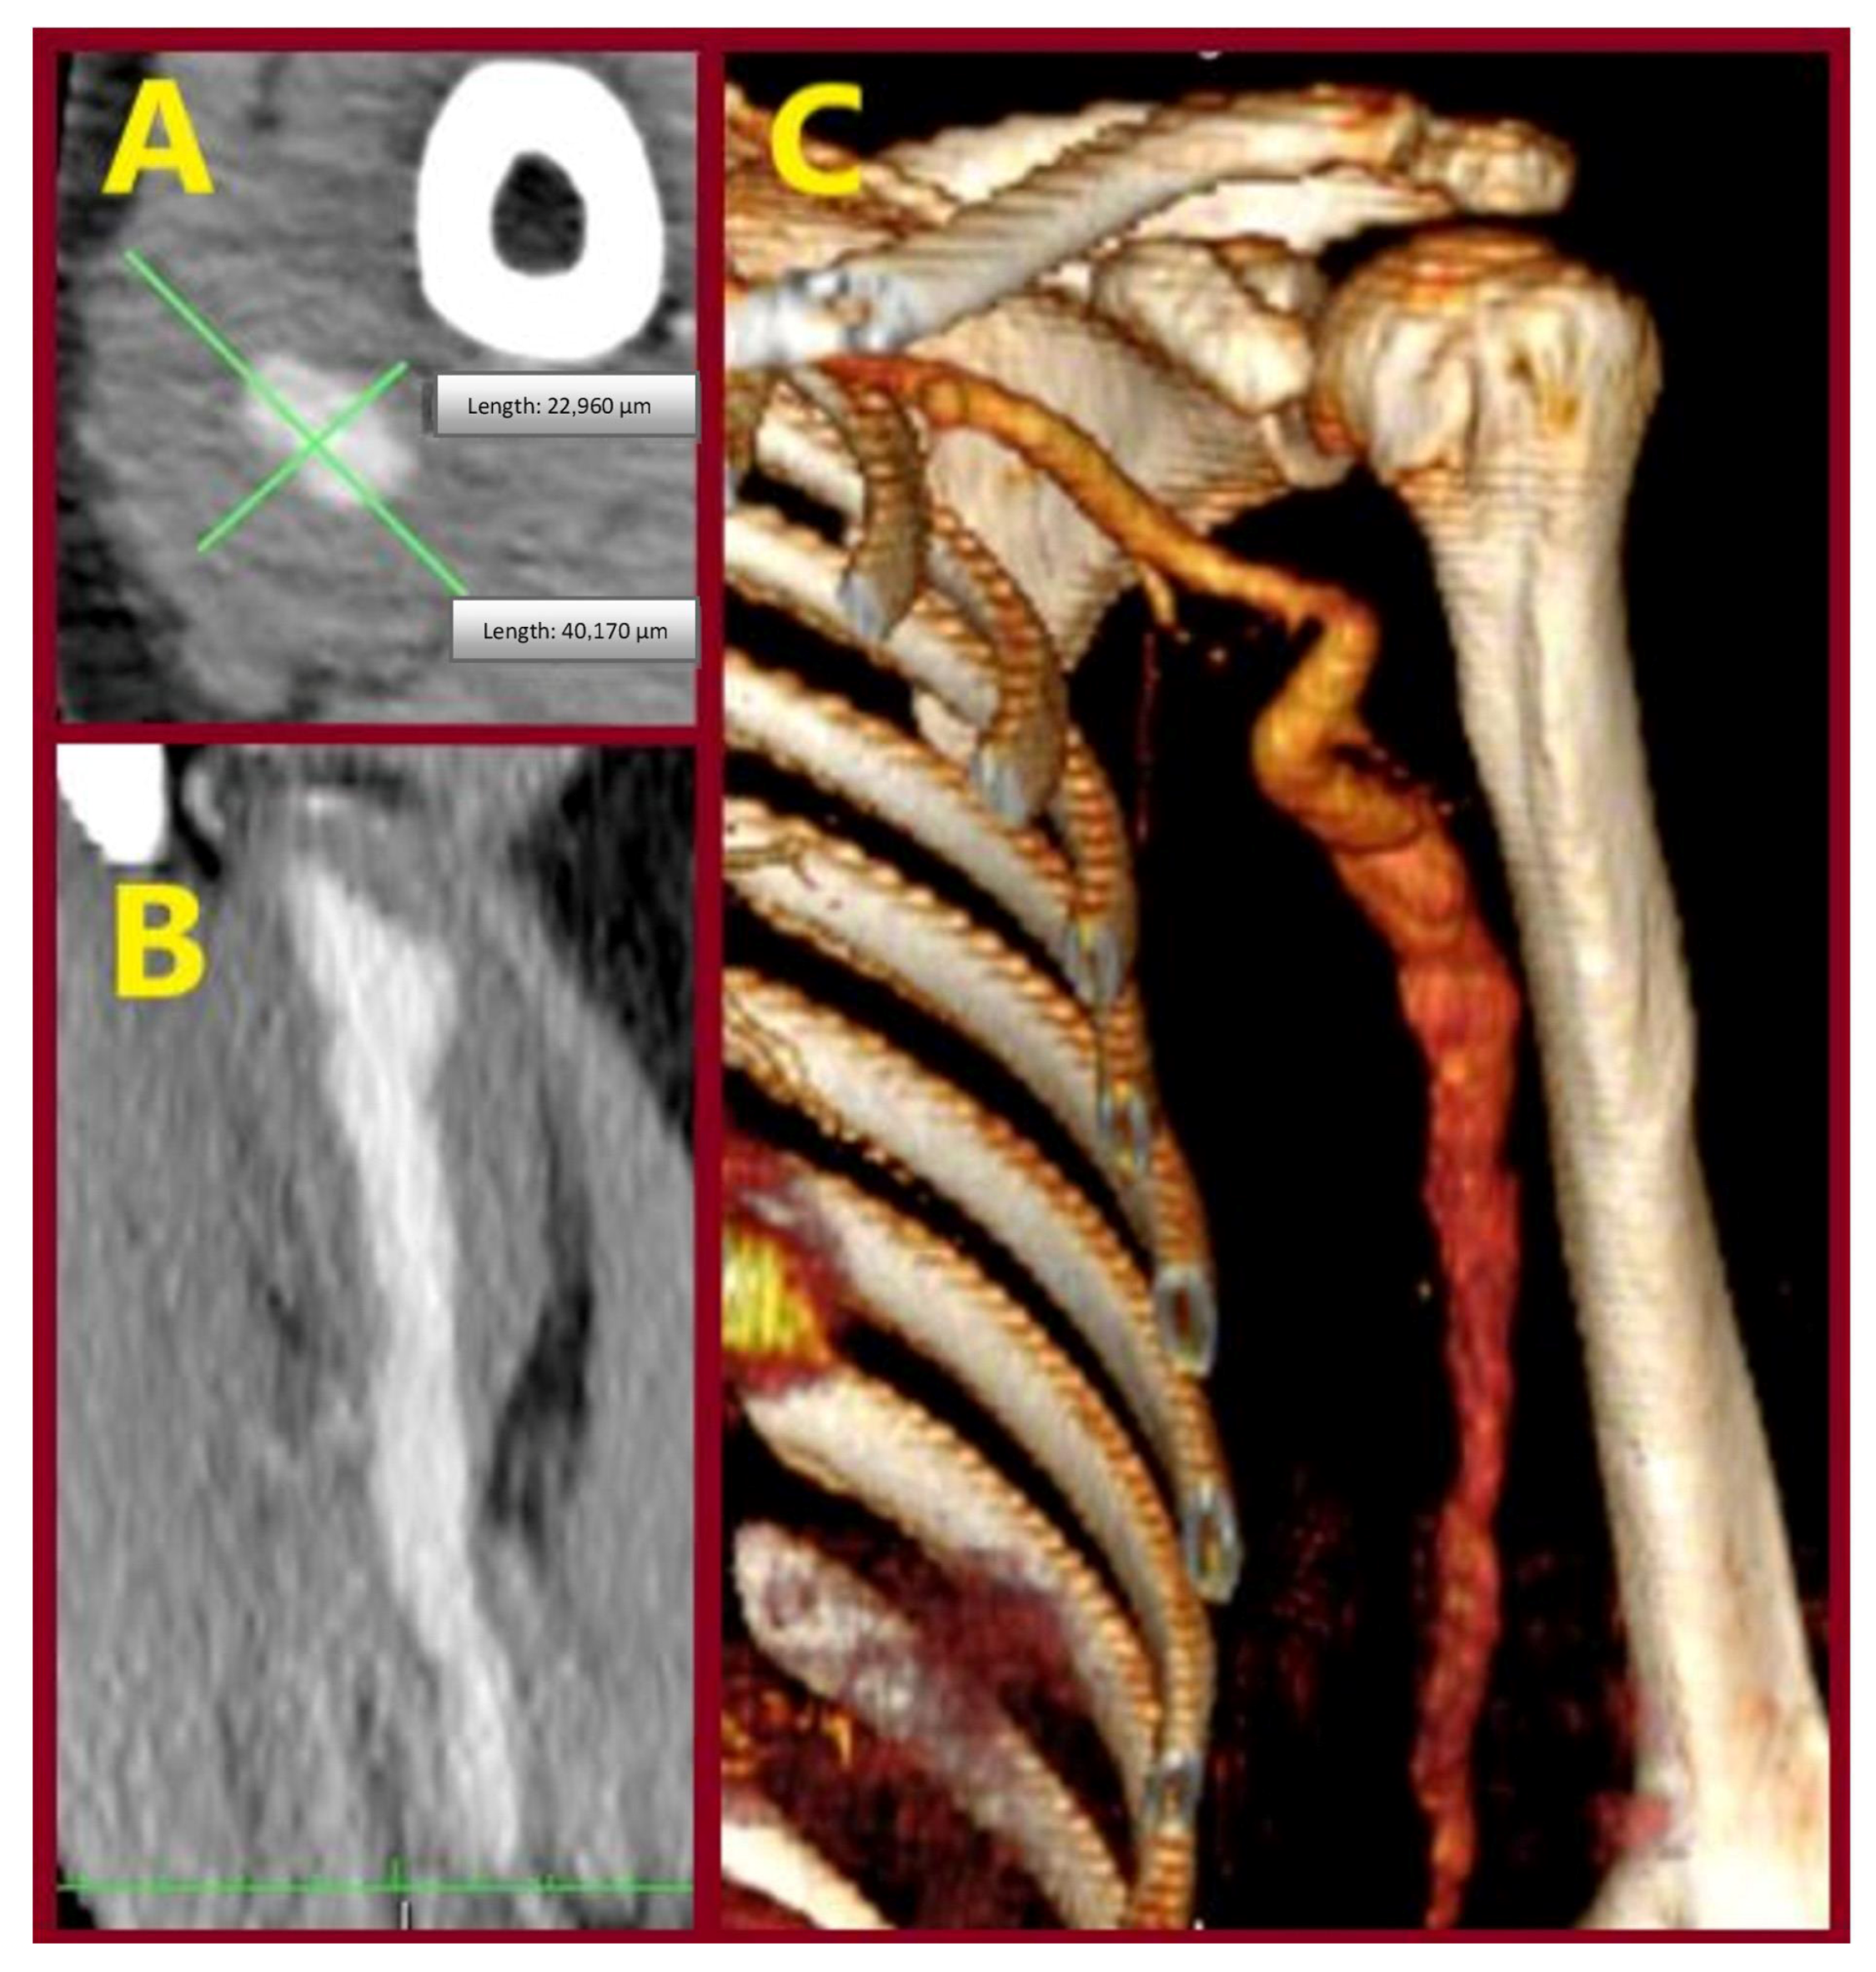

| 1/ 2001 | 28/M | No/ Palpable mass | R/Distal third of BA, extending to ulnar artery | 3.5 | Aneurysm excision & reversed BV interposition between BA & RA, UA ligation | NA |

| 2/ 2007 | 46/M | No/ Palpable mass | L/ Distal half of BA | 4 | Aneurysm excision & reversed BV interposition | NA |

| 3/ 2015 | 65/M | No/ Palpable mass | L/ Two proximal thirds of BA | 4 | Aneurysm excision & reversed BV interposition | NA |